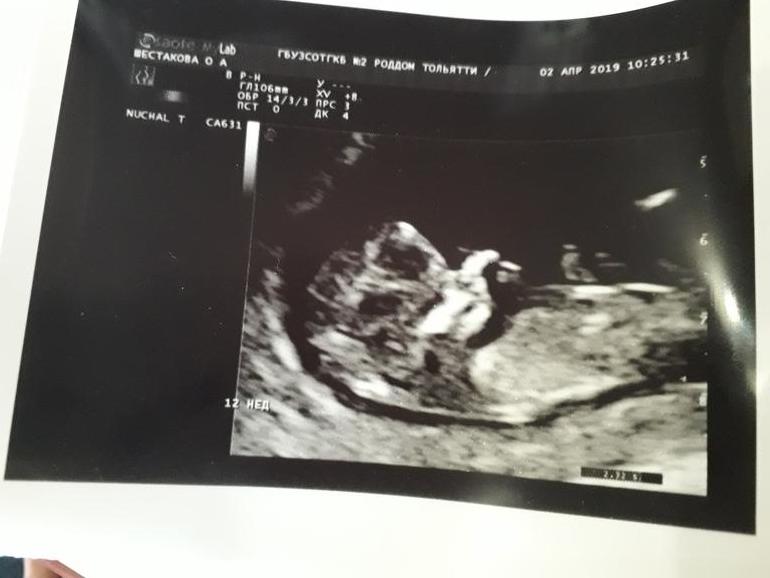

Первый скрининг пройден🙏

Результаты: УЗИ, КТГ, доплера, скринингаПосле прошлой беременности не знала как пойду на это узи, но на удивление вчера и утром была совершено спокойная, но вот пока сидела в очереди трясти начало так что думала с ума сойду. В итоге, с моей бусинкой все хорошо) Срок по М сегодня 11,4 а по узи 12,1 немного опережаем) КТР 5,5; ЧСС 164; воротниковое пространство 1,6; носик померить не смог, кроха ручкой закрыла, но визиализируется; прикреплен к задней стенке) ПДР на 18.10 сделаем прабабушке подарок на др)